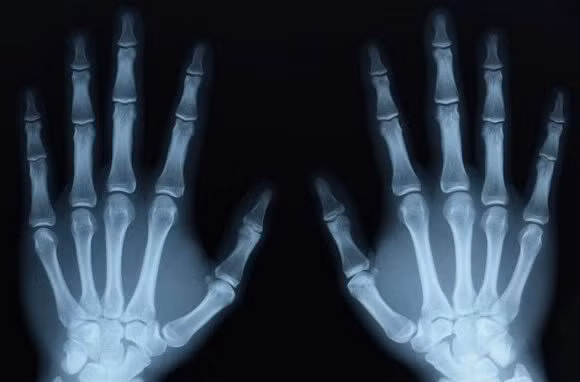

Đừng quên chụp X-quang, chụp cộng hưởng từ (MRI) hoặc chụp cắt lớp vi tính (CT scan) mới có thể xác định chính xác trong hầu hết các trường hợp

Theo PGS.TS Nguyễn Vĩnh Ngọc, tất cả những thông tin phân biệt bong gân cổ tay và gãy xương cổ tay như trên có thể hướng dẫn bạn tự chẩn đoán. Tuy nhiên, đừng quên chụp X-quang, chụp cộng hưởng từ (MRI) hoặc chụp cắt lớp vi tính (CT scan) mới có thể xác định chính xác trong hầu hết các trường hợp – trừ khi xương gãy đâm qua da. Để yên tâm tuyệt đối, bạn vẫn nên đến thăm khám, chụp X-quang tại những khoa cơ xương khớp uy tín.